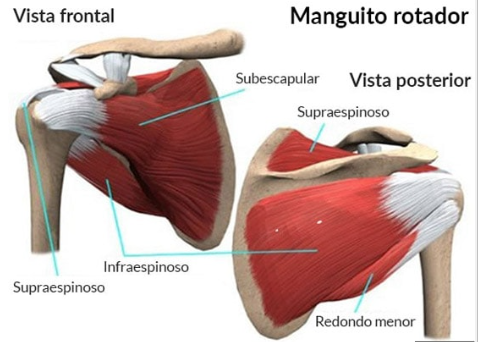

A nivel general, está compuesto por la Clavícula (por la parte frontal), la Escápula (por la parte posterior) y el Húmero (en el lateral). Para dar estabilidad a estas estructuras, existe una gran cantidad de músculos, tendones y ligamentos que rodean la articulación, dándole estabilidad y evitando las luxaciones articulares. Entre los músculos más importantes, encontramos el Manguito Rotador (formado por Supraespinoso, Infraespinoso, Redondo Menor y Subescapular), cuyos músculos nacen en la Escápula y se insertan en el Húmero.

En los casos más leves, se recomendará el tratamiento conservador, que tendrá el tratamiento Fisioterápico como base, y este consiste en ejercicios de fortalecimiento y estabilidad de hombro. Lo más común es que realicemos ejercicios en Rotación (tanto Interna como Externa), Elevaciones Laterales y ejercicios de remo, por ejemplo. Con ellos, aumentaremos la fuerza de la musculatura estabilizadora que se encuentra alrededor de la articulación.